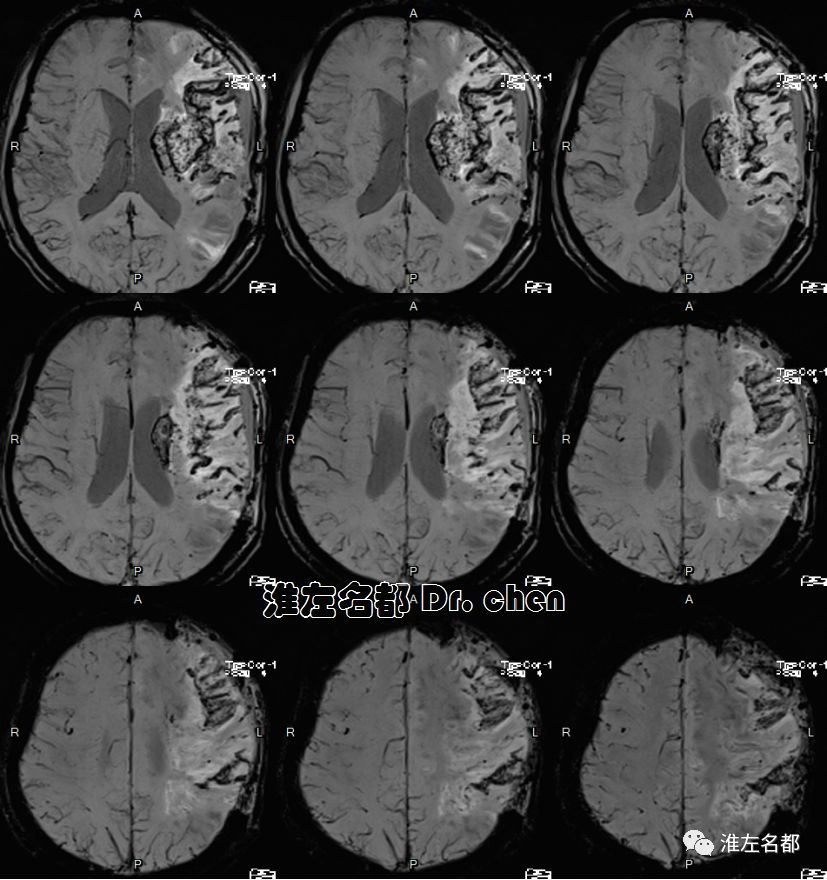

MRI

2019-9-19

△T2WI、T1WI、FLAIR和SWI:左侧半球大面积亚急性梗死伴渗血,局部软化坏死。

△3D-TOF-MRA:左侧大脑中动脉M1段和前动脉A1段管腔显影不规则;左侧大脑中动脉分支显影较对侧稀疏(考虑和大面积梗死后供血需求降低有关)。